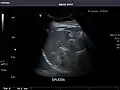

Spleen -

Spleen: Normal in size.